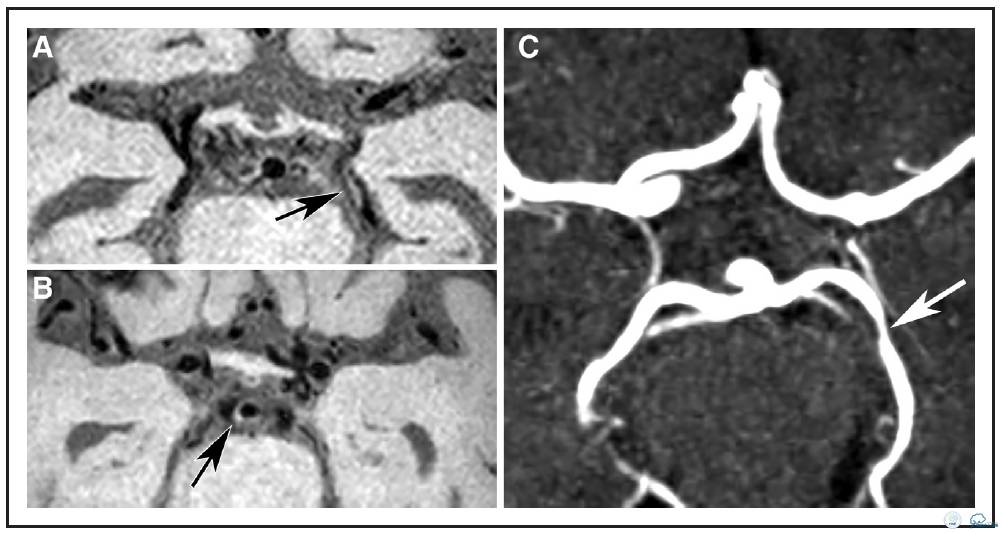

图1:72岁女性患者,左侧前循环梗死。A:横向各向同性的T1加权快速自旋回波采集容积重建图像。B:可见左侧大脑后动脉P2段偏心性,局部增厚病变(箭头),另外,可见基底动脉偏心,局部增厚病变(箭头B)不伴有管腔狭窄(箭头C)。C:横断面时间飞跃磁共振成象显示P2段同一位置为无症状血管壁狭窄病变。